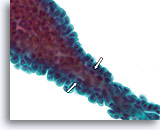

Papilloom, Borst FNA, ThinPrep®.

Als de papillen dun zijn, kunnen fibrovasculaire kernen worden geïdentificeerd in cytologische preparaten. Als de overliggende ductale cellen niet te gestratificeerd zijn, kunnen myoepitheliale cellen mogelijk onder de ductale cellen worden geïdentificeerd (open pijlen), hetgeen pleit voor de diagnose van een papilloom in plaats van een papillair carcinoom.

60X

Papilloom, Borst FNA, ThinPrep®.

Als de papillen dun zijn, kunnen fibrovasculaire kernen worden geïdentificeerd in cytologische preparaten. Als de overliggende ductale cellen niet te gestratificeerd zijn, kunnen myoepitheliale cellen mogelijk onder de ductale cellen worden geïdentificeerd (open pijlen), hetgeen pleit voor de diagnose van een papilloom in plaats van een papillair carcinoom.

60X

Papilloom, Borst FNA, Celblok.

Met een immunokleuring met calponine kunt u de myoepitheliale celpopulatie onder de ductale cellen gemakkelijk zien.

40X

Papilloom, Borst FNA, Celblok.

Met een immunokleuring met calponine kunt u de myoepitheliale celpopulatie onder de ductale cellen gemakkelijk zien.

40X

Papillair carcinoom, Borst FNA, Celblok.

De afwezigheid van een immunokleuring met calponine duidt op een diagnose van een papillair carcinoom.

40X

Papillair carcinoom, Borst FNA, Celblok.

De afwezigheid van een immunokleuring met calponine duidt op een diagnose van een papillair carcinoom.

40X

Papillair carcinoom, Borst FNA, Celblok.

De afwezigheid van kleuring met p63 helpt een papilloom uit te sluiten.

40X

Papillair carcinoom, Borst FNA, Celblok.

De afwezigheid van kleuring met p63 helpt een papilloom uit te sluiten.

40X